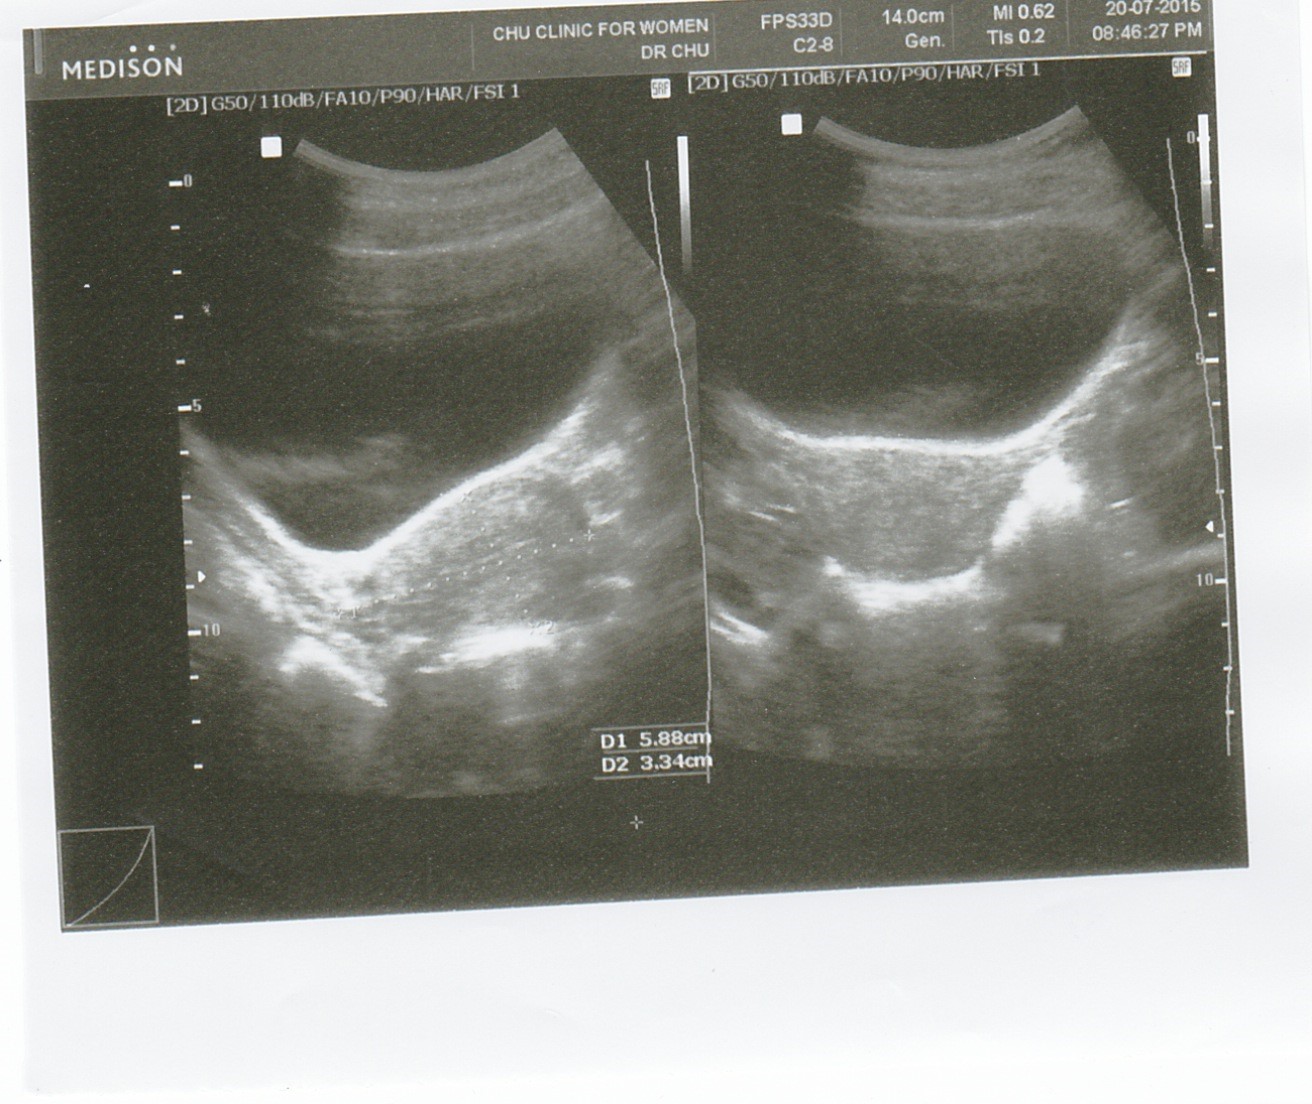

This is my first ultrasound photo. my bladder was full so it was easier to see the cyst (the doctor claimed). He gave me some cream to apply to my miss V and he also gave me some antibiotic to be taken once and he said my itchiness and yellow discharge will stop eventually.

![]() |

| there is the cyst |